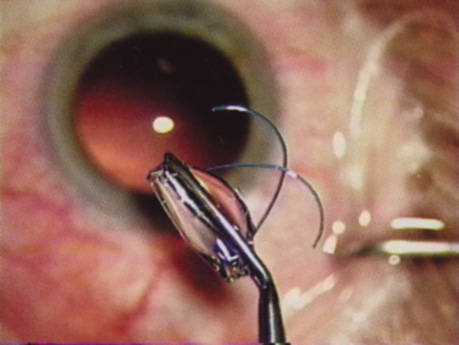

ANTERIOR CAPSULOTOMY

One of the most beneficial techniques developed over the last decade is capsulorrhexis. A continuous curvilinear anterior capsular opening helps prevent intraoperative and postoperative complications. With capsulorrhexis, mechanical strength of the capsular opening is superior to that in a can-opener capsulotomy; thus, a tear to the posterior capsule with subsequent vitreous loss is much less likely.96 Capsulorrhexis allows for nuclear manipulation with less risk of posterior capsule rupture. Cortex removal is made easier as well, because it becomes easier to differentiate cortical material from anterior capsule. Should a posterior capsular tear occur, sulcus fixation is more likely attainable with the presence of a clearly visible residual anterior capsular rim. Placement of both IOL haptics into the capsular bag is more certain with capsulorrhexis because the surgeon can more easily visualize the haptics gliding beneath the anterior capsular rim.

Capsulorrhexis can be performed with a cystitome, capsulorrhexis forceps, or combination-type instruments. Regardless of which instrument is used, several principles can help the surgeon successfully complete capsulorrhexis. It is important to maintain the anterior chamber, because making the chamber shallow increases tension on the zonules and causes the tear to run peripherally. The authors recommend the use of a viscoelastic agent for maintaining chamber depth and, of course, for endothelial protection. Therefore, if the tear begins to run peripherally, the surgeon should redeepen the anterior chamber before attempting to redirect the tear. Additionally, folding the capsule margin can aid the surgeon in redirecting the tear more accurately (Fig. 10).